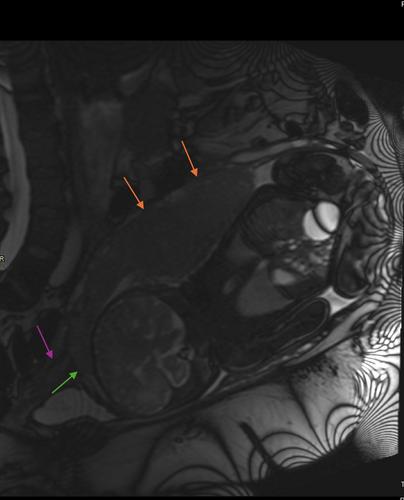

Placenta previa is the partial or complete covering of the internal os of cervix. It is one of the major risk factors for postpartum hemorrhage (PPH), maternal and neonatal morbidity and mortality. A 36-year-old G3P2 Jehovah's Witness female with a gestational age of 36 weeks 6 days and past medical history of chronic hypertension, T2DM, asthma, and past obstetric history of two cesarean sections, large for gestational age babies, and postpartum hemorrhage due to uterine atony, underwent an elective repeat low transverse cesarean section in view of posterior complete placenta previa, complicated by massive postpartum hemorrhage. The patient was immediately transported to the interventional radiology (IR) for uterine artery embolization (UAE) after unsuccessful treatment attempts with uterotonics and JADA system (vacuum induced uterine tamponade). In view of rapidly progressing bleeding, the decision was made for an urgent hysterectomy. Management of postpartum hemorrhage in a Jehovah's Witness patient is particularly complex as these patients refuse administration of blood products and involves medical, ethical, and legal implications.